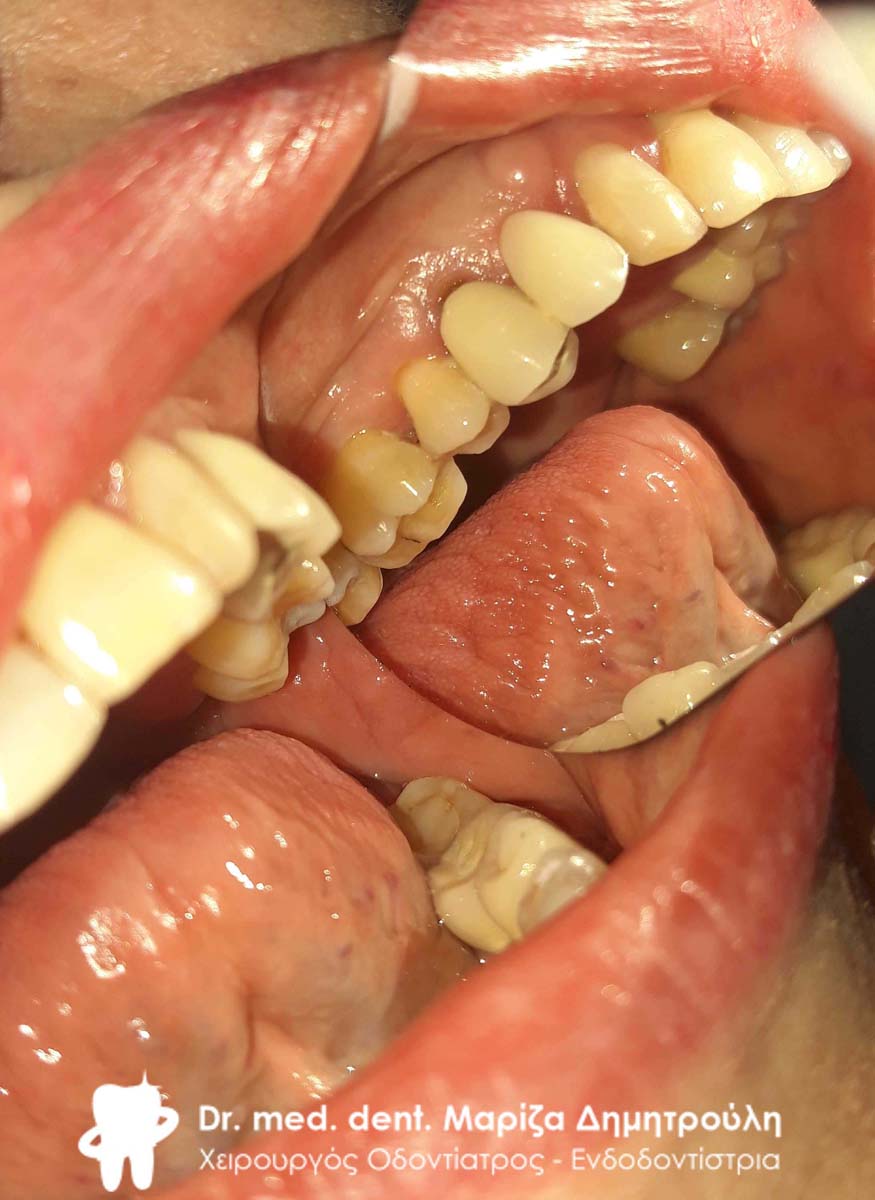

Ο ασθενής είχε πάρα πολλά χρόνια να επισκεφτεί τον οδοντίατρο. Πρόκειται για ένα απαιτητικό περιστατικό, κατά το οποίο ο ασθενής ήταν πολύ συνεργάσιμος καθώς ήθελε να αποκτήσει ένα όμορφο και λαμπερό χαμόγελο. Αρχικά εξάχθηκαν όσα δόντια δεν μπορούσαν να διατηρηθούν πλέον στο στόμα του ασθενή. Στη συνέχεια απονευρώθηκαν τα περισσότερα δόντια και ακολούθησαν ανασυστάσεις όλων των δοντιών. Εφόσον είχε αποκατασταθεί η φλεγμονή των ούλων λήφθηκαν αποτυπώματα και στάλθηκαν στον οδοντοτεχνίτη ο οποίος κατασκεύασε ολοκεραμικές θήκες, οι οποίες ήταν ενωμένες μεταξύ τους (ολοκεραμικό πέταλλο). Ο ασθενής φορούσε προσωρινή γέφυρα στο μεσοδιάστημα που χρειάστηκε ο οδοντοτεχνίτης να κατασκευάσει τη μόνιμη προσθετική εργασία.

Ο ασθενής είναι πολύ χαρούμενος με το λειτουργικό και αισθητικό του αποτέλεσμα. Πρέπει να αναφερθεί οτι όσο καιρό ο ασθενής δεν είχε δόντια δυσκολευόταν πολύ στην άρθρωση του λόγου.

ΠΡΙΝ

Ενδιάμεση κατάσταση αφού ολοκληρώθηκαν οι ανασυστάσεις δοντιών